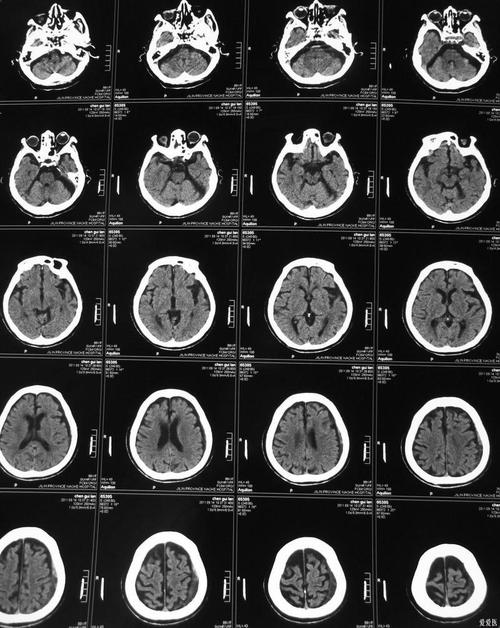

常规的、非增强的CT在脑梗塞发生的极早期(通常在6小时内)通常看不出明显异常,但对于诊断“脑主干”这样的大血管堵塞,它仍然是非常关键和首选的检查方法。

尽管CT在早期看不到梗塞灶本身,但对于怀疑“脑主干梗塞”这种危重情况,CT的以下发现至关重要:

B. 提示早期梗塞的间接征象(“早期缺血征象”)

经验丰富的放射科医生可以在CT上发现一些提示血管堵塞的蛛丝马迹,尤其是在大血管(如大脑中动脉)堵塞时,这些征象出现得比梗塞灶本身早,包括:

- 脑沟消失/变浅: 受影响区域的脑沟因为轻微的细胞水肿而变平或消失。

- 脑实质密度轻度减低: 梗死区域的脑组织密度比周围正常组织略低一点点,但这个变化非常细微,需要仔细观察。

- 豆状核边界模糊: 正常情况下,基底节区的豆状核轮廓清晰,早期缺血时其边界会变得模糊不清。

- 大脑中动脉高密度征: 这是大脑中动脉主干堵塞的一个非常特异的早期征象,在CT上,堵塞的血管因为血液中蛋白质浓缩而呈现出一条高密度的“白线”,像“腊肠”一样,如果看到这个征象,高度提示该血管发生了急性堵塞。